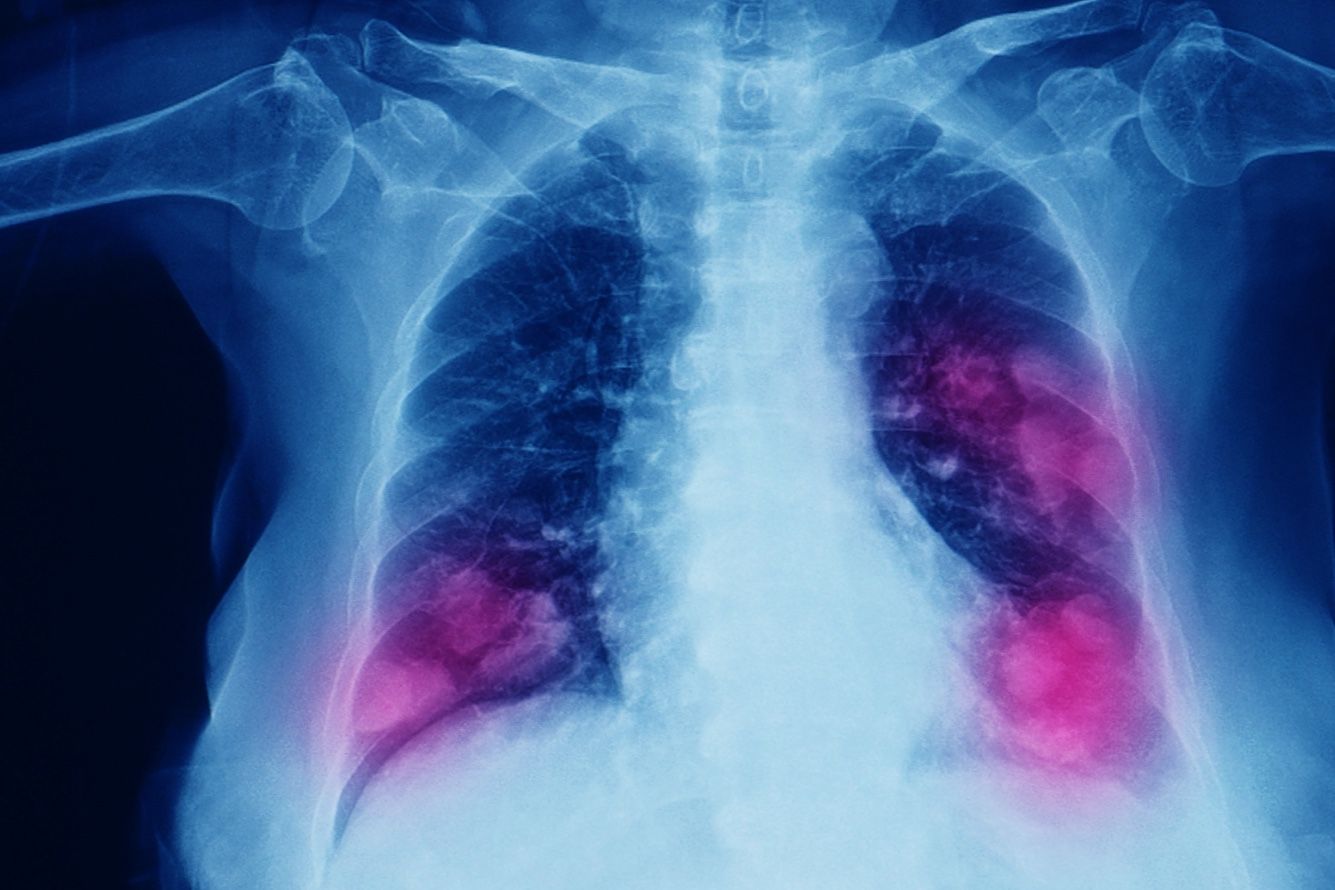

Астма и ХОБЛ — как избежать этих заболеваний и что делать, если они уже есть

Эти болезни очень похожи и даже частично одинаково лечатся. Но и отличий много. Для начала нужно дать определение этим заболеваниям.

Астма — это хроническое воспалительное заболевание нижних дыхательных путей, чаще всего аллергического характера. Они характеризуется приступами или эпизодами бронхоспазма, когда бронхи сужаются и человек начинает задыхаться.

ХОБЛ — это хроническое заболевание всех легких. Его тоже можно и нужно лечить. В отличие от астмы, при ХОБЛ бронхи сужаются, но самостоятельно не расширяются. Кроме того, ХОБЛ характеризуется поражением практически всего дыхательного аппарата. Эмфизема легких — это практически синоним ХОБЛ. То есть воздушность легких ухудшается, потому, что теряется эластичность тканей. Легкие уже не являются надувным воздушным шариком, а становятся чем-то вроде целлофанового пакета, который всегда надут, и сам по себе не сдувается. Если при астме мы можем «надуть» бронхи и они сдуются сами, то при ХОБЛ — нет. Мы можем их надуть, но, чтобы сдуть, надо приложить усилия. А если посмотреть через микроскоп кусочек бронхов больного ХОБЛ, мы снова увидим инфильтрацию, то есть заполнение клетками воспаления всех отделов бронхов. Но в отличие от астмы клетки эти не аллергические. Они тоже вызывают воспаление, но по-другому. При ХОБЛ нет постоянного приступообразного бронхоспазма. Бронхи могут быть сужены за счет отека слизистой, большого количества мокроты. Мышцы бронхов будут тоже увеличены, они начнут сужать просветы между путями, но бронхоспазм иногда есть, иногда нет.